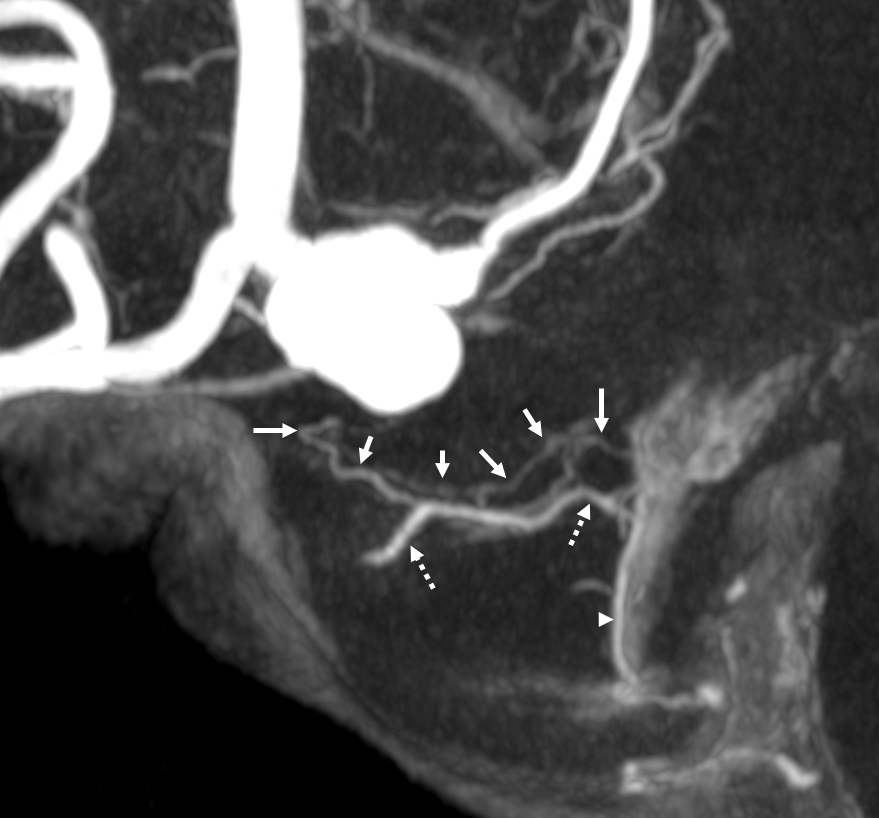

Supply of the Hypophysis and Balance

As always neuroangio is about balance. There may be one or more superior hypophyseal arteries. Usually one is visible by cone beam/flat panel CT. Sometimes more than two. Here there are 3. Nicely shown is supply of the stalk (open arrow). There is also likely contribution to the optic chiasm, which is of course very important. The inferior hypophyseal branches (dashed arrow) from the MHT support the posterior pituitary. The ILT is hypoplastic, with lateral branches of the MHT (white arrowhead) heading towards the meckel cave and the recurrent branch along the tentorial edge (black arrowhead) supplying territory normally done by the ILT